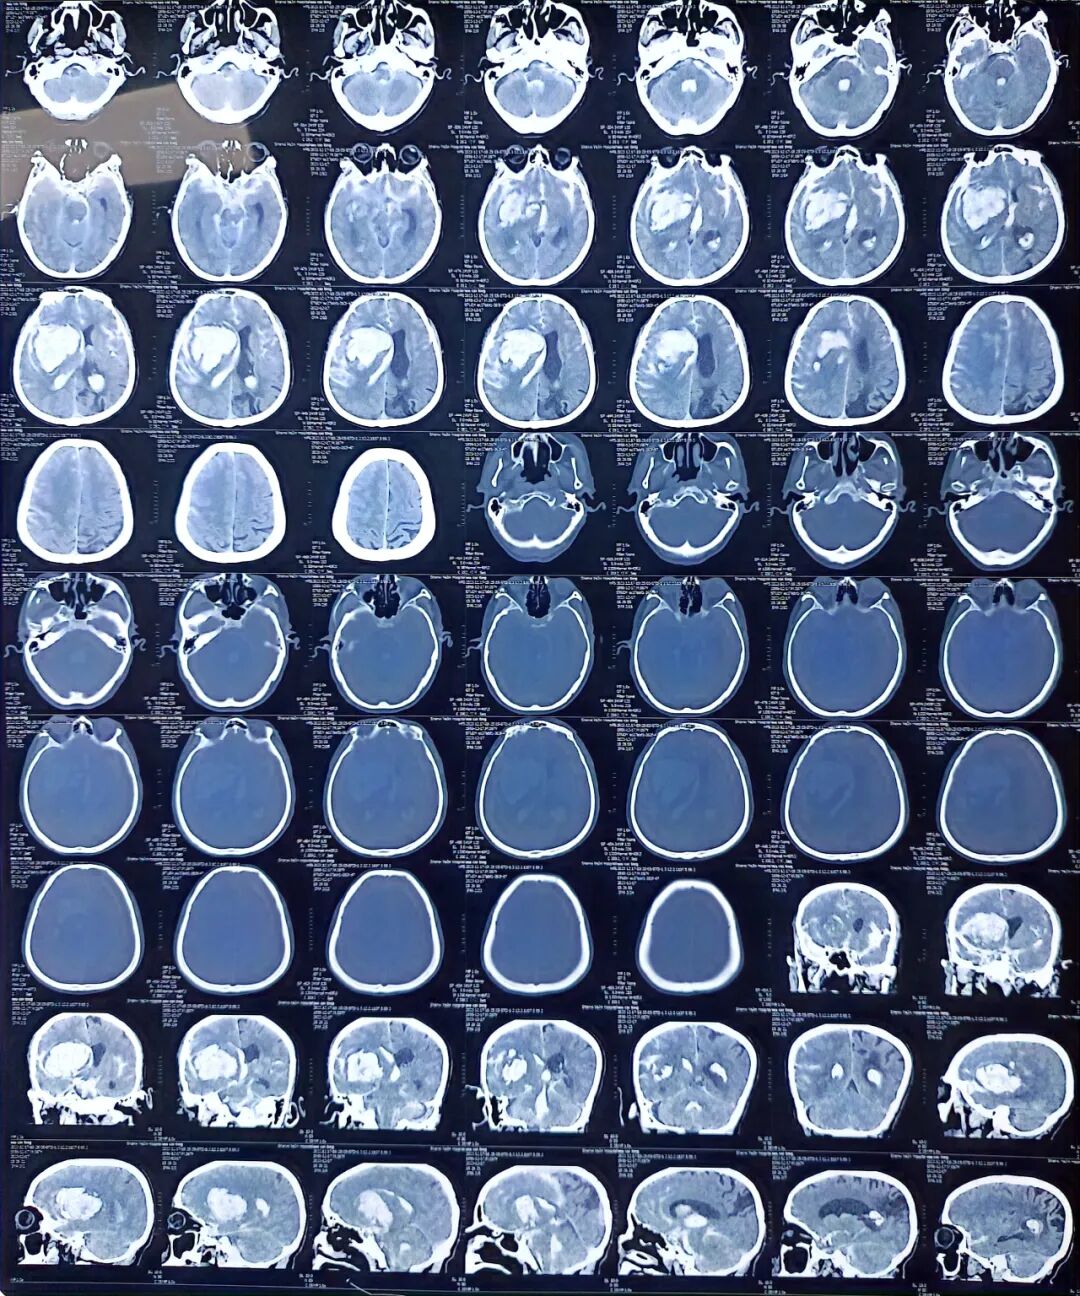

术前检查

急诊医学科行头颅CT检查提示:右侧外囊区脑出血(出血量85ml)破入脑室系统及蛛网膜下腔、左侧枕顶叶软化灶伴局限性脑萎缩。请神经外科急会诊,给予开通绿色通道,遂以“脑出血”收住重症医学科,急行手术治疗。

术后检查

据了解,该患者出血量达到85ml,并且破入蛛网膜下腔、侧脑室,三脑室、四脑室都铸型了,脑部有空隙的地方全都填满了血,当时情况非常危险。医院紧急开通绿色通道,争分夺秒与死神赛跑,先穿刺侧脑室释放脑脊液,快速降颅压,继而穿刺引流脑内血肿,进一步降低颅内压,争取开颅手术时间后,进行开颅去骨瓣减压术+脑内血肿清除术+颅内压监测传感器(ICP)植入术,充分保护脑组织,最大限度减少后遗症。